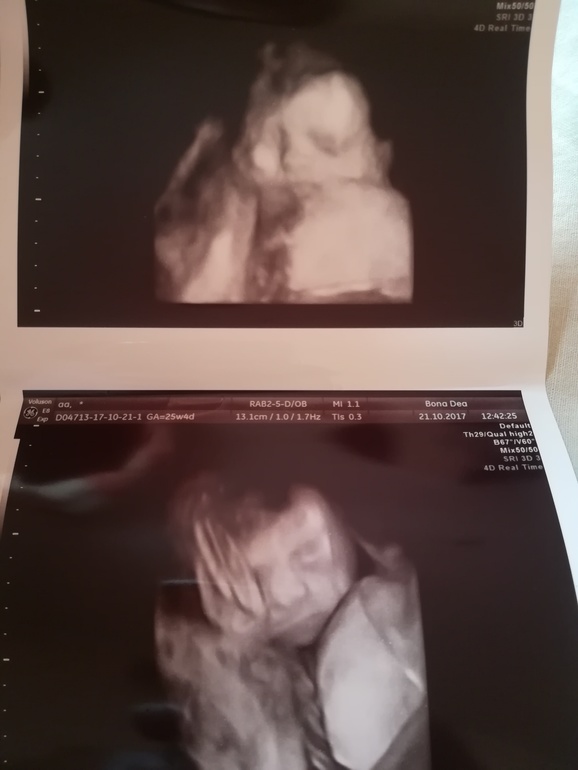

Вчера были на узи. Малышка наша притихла на 2 дня. Как я её только не будила. Бесполезно. Нервишки мои сдали и мы бегом, благо нашли окошко в клинике, помчались на узи. Слава богу все хорошо. По М 25/4 по узи 26 недель. Вес 790гр. Перевернулась головой вниз. Пусть так и лежит до родов) нечего гулять) шейка в норме 36,5мм. Кстати, пессарий мне так и не поставили.

Наделали кучу фоточек нашей красавицы

Безумно любим её и ждём. Такие щёчки, ммм. Затискаю))